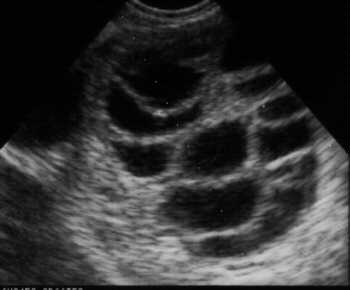

- يجب إستخدام هذه الأدوية بحرص لأنها قد تؤدي إلى التنشيط الزائد للمبيض، ولهذا يجب متابعة إستجابة المبيضين لهذه الهورمونات بإستخدام جهاز الموجات فوق الصوتية (السونار) وخاصة من خلال المهبل ، كما يمكن إضافة تحليل هورمون الإستروجين والذي إذا إرتفع مقداره عن مستوى معين يكون ذلك بمثابة المنبه لزيادة إحتملات حدوث التنشيط الزائد للمبيض والذي يمكن أن يشكل خطورة.

- لا يجب إستخدام هذه الأدوية إلا تحت الإشراف المباشر للطبيب المتخصص ومتابعته لتنشيط المبيض بإستخدام جهاز الموجات فوق الصوتية (السونار) من خلال المهبل.